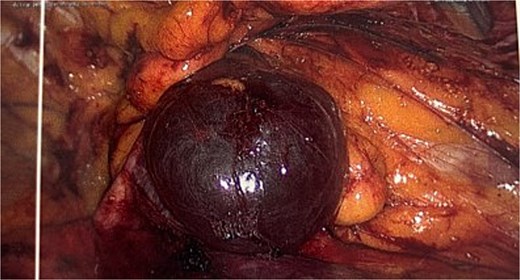

She proceeded for a laparoscopic TAPP excision of the hydrocele. After the abdominal cavity was entered and insufflated the preperitoneal flap was raised the hydrocele was identified medial to the inferior epigastric vessels (Fig. 2). With medial traction the hydrocele was able to be fully reduced and dissected free from the round ligament. The hydrocele was retrieved and sent for histological review. The resultant defect following excision (Fig. 3) was re-enforced with a 12 × 16 cm ProGrip mesh (Fig. 4) before the closure. She was observed post operatively and discharged home on the same day as her surgery.

Intraoperative picture showing the progrip mesh in situ now covering the defect.